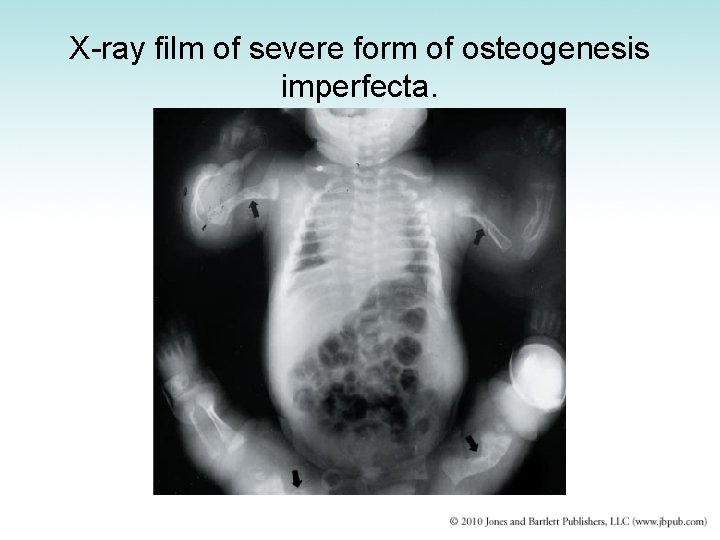

Congenital Malformations (1 of 2) • Achondroplasia – Faulty endochondral bone formation – Impaired growth of extremities and formation of skull bones – Causes dwarfism with disproportionately short limbs • Osteogenesis imperfecta – – – Thin and delicate bones easily broken May be born with multiple fractures Malformation of fingers and toes Extra digits or polydactyly Easily removed Fused digits more difficult to correct

X-ray film of severe form of osteogenesis imperfecta.